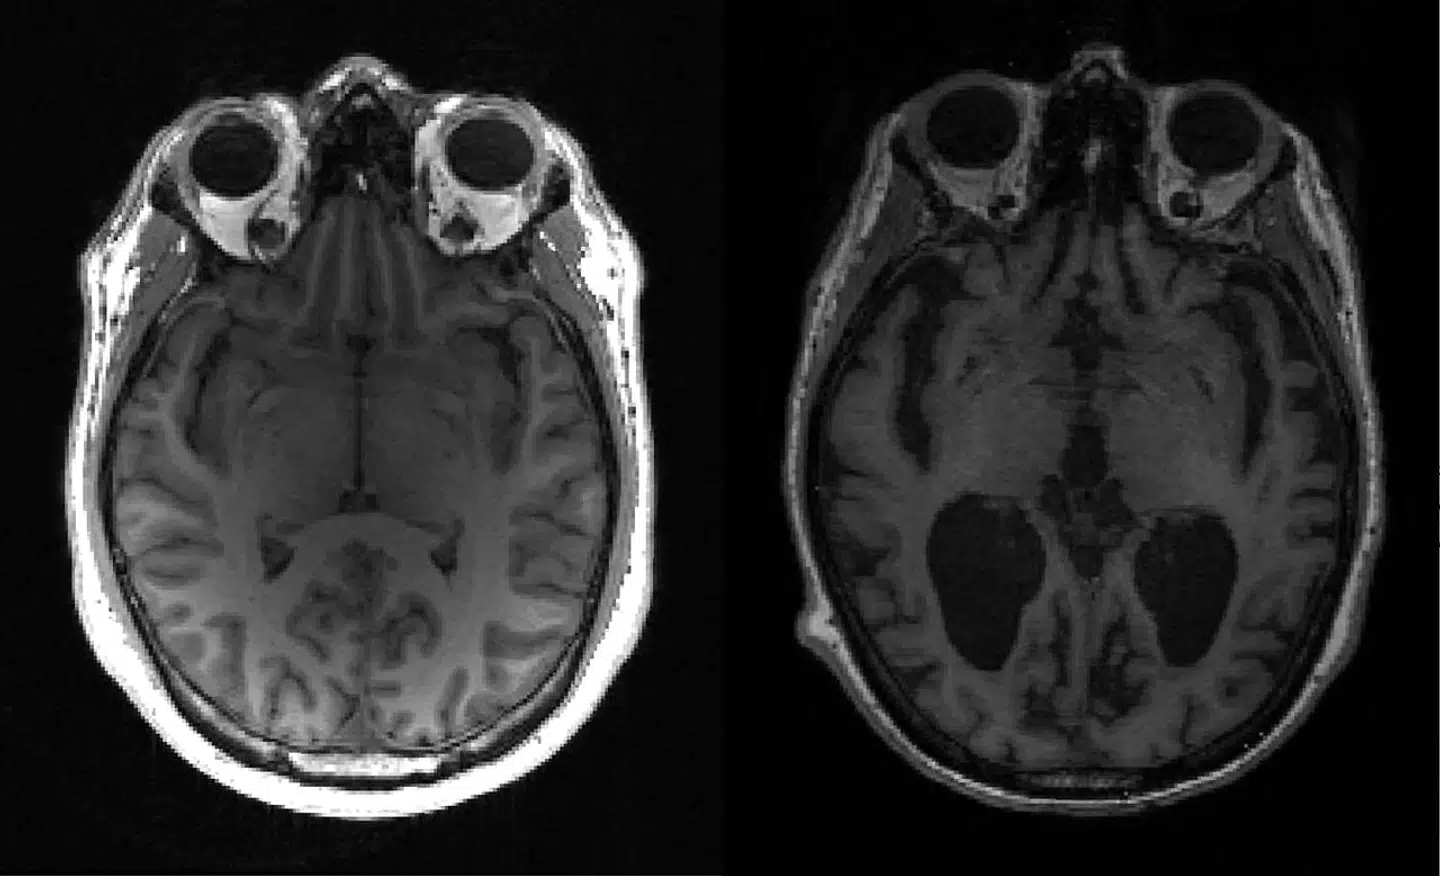

Et karakteristisk symptom på alzheimers er, at der ophobes klumper af proteinet beta-amyloid i hjernen. Det har længe været den dominerende hypotese blandt forskere, at disse klumper er den primære årsag til sygdommens invaliderende demens.